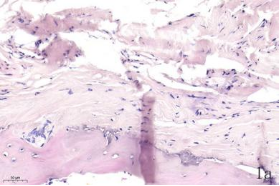

NDN(Necdin)屬于黑色素瘤抗原(MAGE)家族,由60多個基因構(gòu)成共享高度保守的MAGE同源結(jié)構(gòu)域(MHD)[6,7]。最近幾年的研究提出NDN是一種新的抑癌基因,其在卵巢癌[8]、乳腺癌[9]和黑色素瘤[10]等的組織和細胞系中低表達,過表達NDN可以抑制其生長,但NDN在骨肉瘤中的作用及機制尚不清楚。為探討NDN在骨肉瘤中的作用及途徑,我們收集了骨肉瘤患者的石蠟標本以及臨床信息,對其進行了免疫組化檢測及生存分析。通過對骨組織和骨肉瘤HE染色發(fā)現(xiàn),骨組織組,骨密質(zhì)呈板層狀,陷窩中可見骨細胞呈梭形排列( 圖1 a 1b) ;骨肉瘤組,瘤細胞呈多角形,核大深染,核分裂多見,瘤細胞呈車輻狀排列,瘤細胞間可見少量腫瘤性骨質(zhì)形成(圖1c1d)。同時通過免疫組化發(fā)現(xiàn),NDN表達主要位于細胞的胞核中。NDN在骨肉瘤組織中的表達率為29.4%(15/51)(圖1c1d),明顯低于瘤旁骨組織陽性表達率80%(8/10)(圖1a1b)。